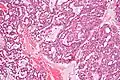

| Low magnification micrograph of a polymorphous low-grade adenocarcinoma, showing the typical variation of architectural arrangement. H&E stain. | |

Polymorphous low-grade adenocarcinoma (PLGA) is a rare, asymptomatic, slow-growing malignant salivary gland tumor.[1] It is most commonly found in the palate.[2]

- It has a varied microscopic architectural appearance, i.e. it is polymorphous.

PLGAs consist of a monomorphous cell population that has a varied histologic morphology.

Microscopically, its histology can be confused with an adenoid cystic carcinoma and a pleomorphic adenoma.